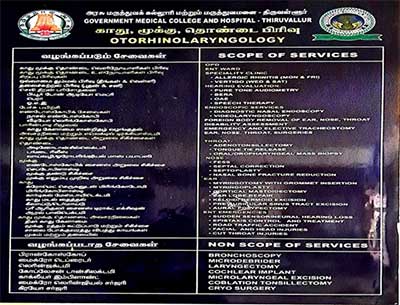

Department of ENT has an exclusive Outpatient clinic situated in the second floor of the Main block with OPD & Ward in the 2nd floor of the Main block and exclusive Laminar airflow operation theatre complex in the 5th floor and Surgical ICU for ENT with 6 beds with all life saving necessary equipments.